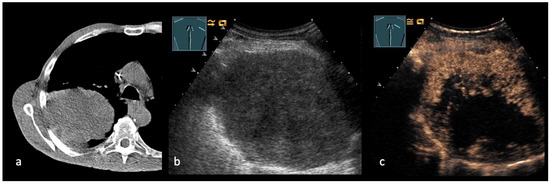

Emerging Role of Transcutaneous Ultrasound in the Diagnostic of Lung Cancer

by Corinna Trenker-Burchert, Marius Dohse, Hajo Findeisen, Andreas Schuler and Christian Görg

Cancers 2025, 17(23), 3873; https://doi.org/10.3390/cancers17233873 - 2 Dec 2025

Lung cancer is one of the most commonly diagnosed malignancies worldwide and continues to be a leading cause of cancer-related mortality. Precise staging is crucial for predicting outcomes and directing treatment decisions. Current international guidelines mainly recommend imaging techniques like CT and PET-CT, [...] Read more.

Lung cancer is one of the most commonly diagnosed malignancies worldwide and continues to be a leading cause of cancer-related mortality. Precise staging is crucial for predicting outcomes and directing treatment decisions. Current international guidelines mainly recommend imaging techniques like CT and PET-CT, with limited references to transcutaneous ultrasound, which is only suggested in particular clinical cases. Ultrasound provides real-time imaging, high resolution in near-field structures, and the ability to assess thoracic wall infiltration, supraclavicular and cervical lymph nodes, pleural effusions, and metastatic lesions. Furthermore, ultrasound-guided biopsies can enable quick and safe histological confirmation of accessible lesions. Based on these advantages and a review of current literature, we propose that integrating ultrasound into staging algorithms could improve diagnostic efficiency, decrease invasive procedures, and support prompt treatment planning. We also highlight the need for further research in this area. Full article

Show Figures

Figure 1